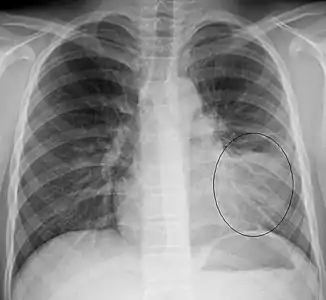

AP CXR showing pneumonia of the lingula of the left lung